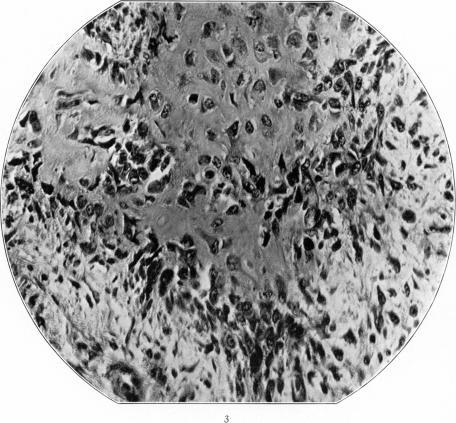

A Group of Metaplastic and Neoplastic Bone- and Cartilage-Containing Tumors of Soft Parts.

Am J Pathol. 1933;9(Suppl):765-776.3.